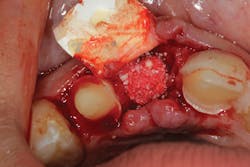

Because of this alveolar resorptive pattern after tooth extraction, bone grafting the extraction socket after tooth extraction procedures has become a solution that attempts to limit the amount of hard- and soft-tissue loss. There are many systematic reviews in the literature that compare the results of residual ridge dimension following tooth extraction after the use of a bone graft (with or without a membrane) versus extraction alone without grafting.7

• site development to increase hard and soft tissue for pontic sites in fixed bridge prosthetics (figures 9–14);• correcting bone defects impinging upon anatomical structures after tooth extraction, such as oroantral communication (figure 18); and

• preserving tissue structure for subsequent dental implant therapy.Decision matrix